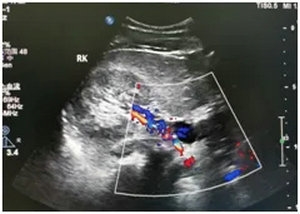

▲ 彩超:右肾动脉中段串珠样狭窄

1.定位:右侧肾动脉中段

2.定性:肾动脉纤维肌发育不良

3.定量:重度狭窄

且该患者右肾已经明显萎缩。